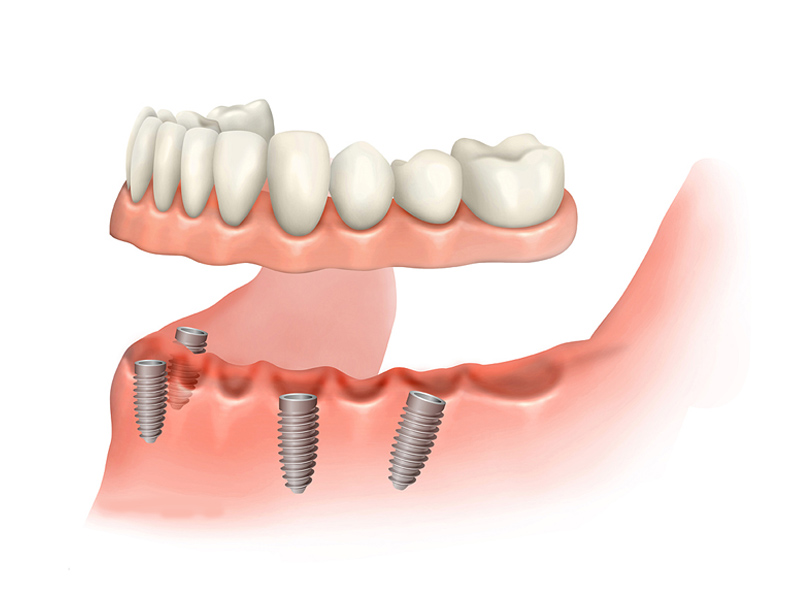

Implantology All on 4

This method is aimed both at edentulous patients who want a fixed prosthetic restoration, and at patients who have an insufficient amount of bone necessary to insert implants and are not candidates for conventional implant-prosthetic therapy.

Using the All-On – 4 method; Dental implants are inserted in the same day and in a few hours, a temporary but fixed prosthetic job is performed immediately which will remain until the implants are perfectly integrated into the bone. After about 4-6 months, definitive prosthetic rehabilitation will be performed, which will be screwed onto existing implants. The screw fixing will allow you to remove the restoration (fixed bridge) when necessary.

The specificity of this procedure is that the teeth are fixed on four implants. Thanks to the particular method of inserting the implants, bone reconstruction is not necessary, which is instead a requirement when it is necessary to reconstruct in patients who have total tooth loss.